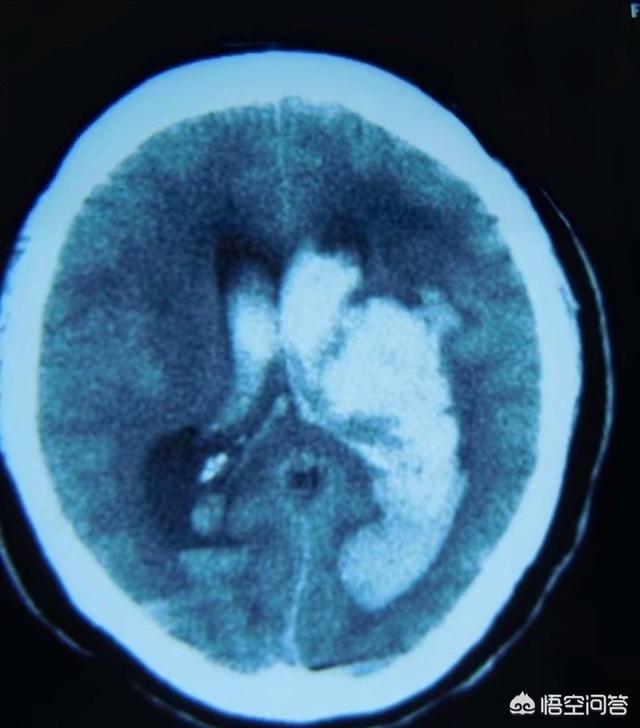

Les hémorragies cérébrales comprennent les hémorragies parenchymateuses et les hémorragies sous-arachnoïdiennes.

L'hémorragie parenchymateuse cérébrale est souvent associée à l'hémorragie cérébrale hypertensive, à l'hémorragie due à l'amylose vasculaire et à l'hémorragie due à la malformation artérioveineuse.

L'hémorragie cérébrale est un saignement dans le parenchyme cérébral dû à des facteurs non traumatiques, le plus fréquent étant l'hémorragie cérébrale hypertensive.

L'hypertension artérielle à long terme entraîne souvent une athérosclérose des petites artères du cerveau, et d'autres facteurs tels que le diabète entraînent également de petites lésions artérielles, sur lesquelles une augmentation soudaine de la pression artérielle peut provoquer une rupture des artères cérébrales.

Les hémorragies cérébrales sont généralement divisées en hémorragies parenchymateuses et hémorragies sous-arachnoïdiennes. Dans le premier cas, il s'agit souvent d'hémorragies cérébrales hypertensives, d'hémorragies dues à l'amylose vasculaire et d'hémorragies dues à des malformations artérioveineuses (qui ne réapparaissent généralement pas après la guérison).